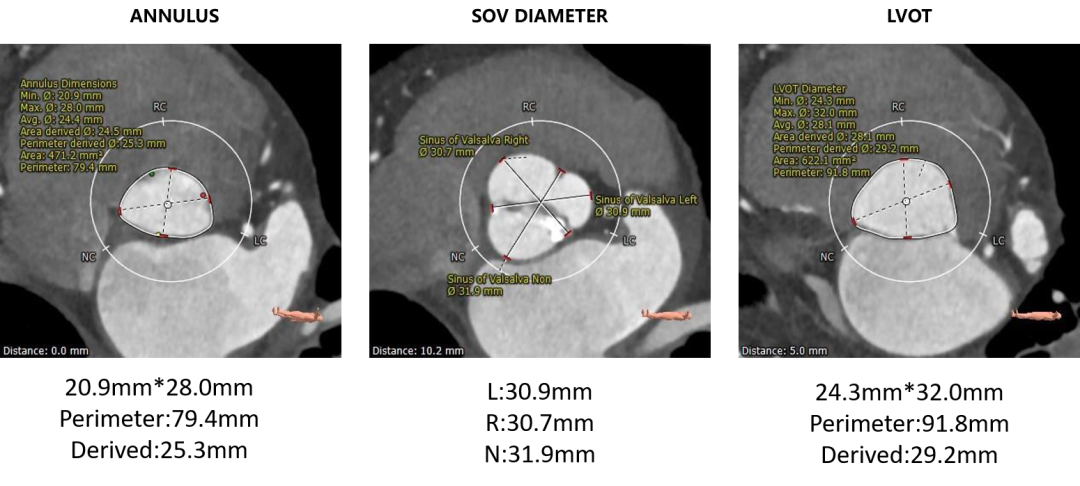

主动脉根部测量

• 术前CT显示为Type 1型二叶式主动脉瓣,瓣叶严重增厚,左右冠窦瓣叶融合并形成纤维嵴。中度钙化,钙化分布不均匀,最严重处为无冠窦瓣叶处。

• 左右冠开口高度可,左右冠瓣叶长度<左右冠开口到左冠瓣叶附着缘距离。

• 瓣环水平夹角为58°,右侧髂总动脉条状钙化,入路血管管径良好。